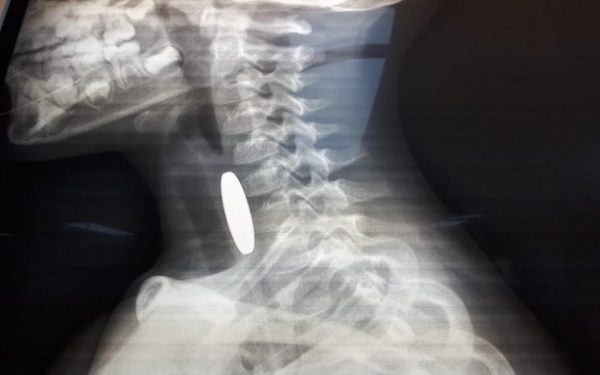

أنقذت مرتبات دورية نجدة تابعة لشرطة مادبا أثناء الوظيفة الرسمية حياة طفل يبلغ من العمر ثلاثة أعوام ونصف، بعد أن تعرض لحادثة اختناق إثر ابتلاع عملة معدنية في منطقة لواء ذيبان. وفي التفاصيل، قال والد الطفل محمد الجديعات لإذاعة الأمن العام، إنه وبعد أن لاحظ أن طفله يجد صعوبة بالتنفس قام بشكل فوري بإسعافه باتجاه مستشفى الأميرة سلمى الحكومي، حيث صادف وجود دورية نجدة على مقربة من منزله وعلى الفور استنجد بهم، ليقوم أفراد الدورية بتقديم الإسعافات الأولية اللازمة باحترافية لمثل هذه الحالات بعد أن ابلغهم أنه قد ابتلع قطعه معدنية . من جانبه قال الوكيل علاء السلايطة، أحد أفراد الدورية: “أثناء وجودنا في المنطقة استنجد بنا والد الطفل وهو يحمل ابنه، فقمنا مباشرة بتقديم الإسعافات الأولية المخصصة للأطفال دون سن الخامسة، وفقاً للتدريبات والدورات التي نتلقاها من مديرية الأمن العام للتعامل مع مثل هذه الحالات حتى بدأت حالته الصحية بالاستقرار واستكمال عملية إسعافه باتجاه المستشفى بواسطة المحطة الأمنية بعد أن تم التنسيق مع غرفة العمليات والسيطرة.